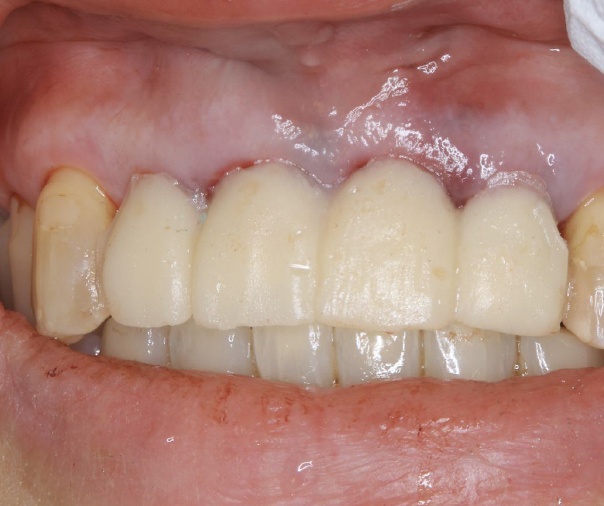

歯周病による前歯部抜歯即時インプラント症例(50代女性)

50代女性です。歯周病で歯の揺れが治まらず、前歯4本の抜歯となりました。

当日、抜歯とインプラントを同時に入れました。

4本抜歯して2本のインプラントを入れました。

手術直後、1週間後の抜糸時、3か月後の写真です。

抜歯、インプラント埋入から6か月後に完成しました。